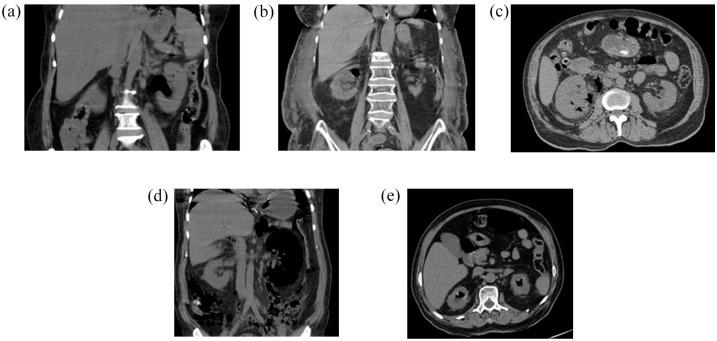

A retrospective analysis of 90 consecutive patients diagnosed clinico-radiologically with EPN from January 2011 to September 2020. Five scoring systems were evaluated for their predictive ability for the need for ICU management and mortality risk: National Early Warning Score (NEWS), Modified Early Warning Score (MEWS), 'quick' Sequential Organ Failure Assessment score (qSOFA), Systemic Inflammatory Response Syndrome score (SIRS), and Sequential Organ Failure Assessment score (SOFA). CT images were classified as per Huang & Tseng and evaluated as stand-alone or added to the different predictive models. Receiver operating characteristic (ROC) curves were plotted for each critical care score and CT-Class using logistic regression, to obtain the area under curve (AUC) value for comparison of ICU admission predictability. Patients were analyzed up till discharge.

对2011年1月至2020年9月期间临床放射学诊断为EPN的90例连续患者进行回顾性分析。评估了五个评分系统对ICU管理需求和死亡风险的预测能力:国家早期预警评分(NEWS)、改良早期预警评分(MEWS)、“快速”序贯器官衰竭评估评分(qSOFA)、全身炎症反应综合征评分(SIRS)和序贯器官衰竭评估评分(SOFA)。CT图像根据黄氏和曾氏分类法进行分类,并作为独立因素或添加到不同的预测模型中进行评估。使用逻辑回归为每个重症监护评分和CT分类绘制受试者操作特征(ROC)曲线,以获得曲线下面积(AUC)值,用于比较ICU入院预测性。对患者进行直至出院的分析。